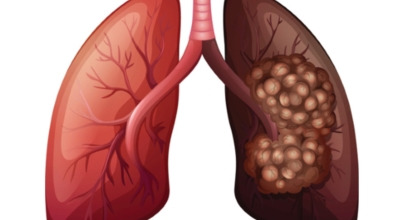

폐란?

척추동물 중 공기호흡을 하는 동물의 호흡기관으로, 허파 또는 폐장이라고도 하며, 구조적으로 기관지와 혈관이 모여 이루어져 있습니다. 폐는 산소와 이산화탄소(탄산가스)를 교환하는 가장 중요한 기관입니다. 사람에게는 좌우 한 쌍이 있으며, 전체적으로 반원뿔 모양을 하고 있습니다. 흉강 중앙에 있는 종격을 사이에 두고 가슴의 좌우에 자리 잡고 있는데, 좌측에 심장이 있어 오른쪽 폐가 조금 더 큽니다.